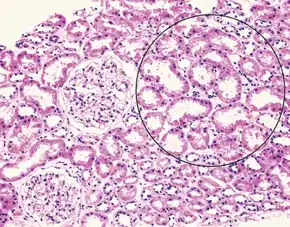

Liver histology is altered in HRS while kidney histology is normal. The upper image is a trichrome stain (chicken wire appearance) of cirrhosis of the liver, the most common cause of HRS. | |

Many other diseases of the kidney are associated with liver disease and must be excluded before making a diagnosis of hepatorenal syndrome. Individuals with pre-renal kidney failure do not have damage to the kidneys, but as in individuals with HRS, have kidney dysfunction due to decreased blood flow to the kidneys. Also, similarly to HRS, pre-renal kidney failure causes the formation of urine that has a very low sodium concentration. In contrast to HRS, however, pre-renal kidney failure usually responds to treatment with intravenous fluids, resulting in reduction in serum creatinine and increased excretion of sodium.[3] Acute tubular necrosis (ATN) involves damage to the tubules of the kidney, and can be a complication in individuals with cirrhosis, because of exposure to toxic medications or the development of decreased blood pressure. Because of the damage to the tubules, ATN affected kidneys usually are unable to maximally resorb sodium from the urine. As a result, ATN can be distinguished from HRS on the basis of laboratory testing, as individuals with ATN will have urine sodium measurements that are much higher than in HRS; however, this may not always be the case in cirrhotics.[5] Individuals with ATN also may have evidence of hyaline casts or muddy-brown casts in the urine on microscopy, whereas the urine of individuals with HRS is typically devoid of cellular material, as the kidneys have not been directly injured.[3] Some viral infections of the liver, including hepatitis B and hepatitis C can also lead to inflammation of the glomerulus of the kidney.[18][19] Other causes of kidney failure in individuals with liver disease include drug toxicity (notably, the antibiotic gentamicin) or contrast nephropathy, caused by intravenous administration of contrast agents used for medical imaging tests.[3]